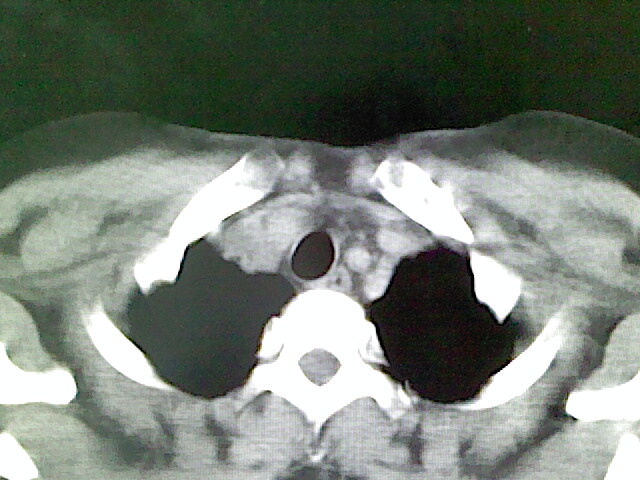

女,52岁,咳嗽,咳痰多日

左下肺陈旧纤维索条!

左肺舌段炎性改变

我见过几例,为炎症后纤维条索

慢性炎症后改变

考虑慢性炎性病灶粘连牵拉改变。

左肺舌叶纤维锁条病变。

左肺上叶下舌段炎症并局部胸膜反应。

左肺舌叶纤维索条影。

左肺舌叶段陈旧性病变

左肺舌段炎性反应。片子的质量太不好了。

左肺舌段炎性

炎性改变

左肺舌叶纤维索条影